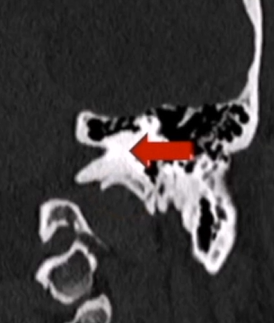

第一步是术前精准评估:通过MRI确认脑干无水肿,CT扫描逐一评估肿瘤钙化程度、岩尖气化范围、颈静脉球与内耳道的位置关系,每一个解剖细节,都是术中安全操作的前提。

到2019年手术时,他的情况已积累了四重困难:其一,肿瘤体积巨大,脑干已遭受严重压迫——脑干掌管呼吸、心跳与意识,对它的每一分压迫都是对生命的威胁;其二,肿瘤被血管团团包围,咽升动脉和颈内动脉硬脑膜分支如同散布在术野中的地雷,稍有不慎即可引发难以控制的大出血;其三,肿瘤已出现钙化,质地变硬,切除难度倍增,对周围神经血管的牵拉风险也随之升高;其四,肿瘤已浸润硬脑膜,并伴有岩尖骨质气化,颅底重建压力叠加,脑脊液漏的风险始终悬在头顶。